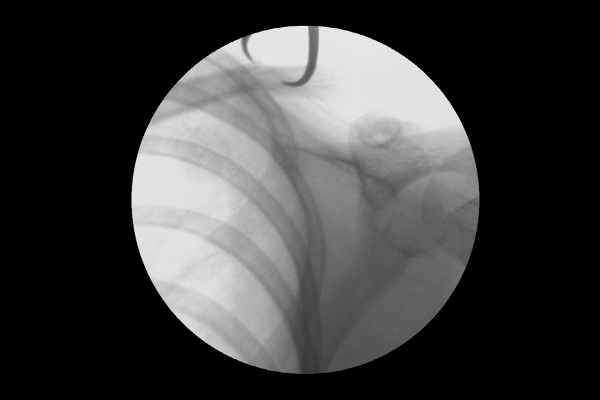

환자분의 쇄골 상태를 정확하게 파악하기 위해 X-RAY 촬영을 시행하였고, 검사 결과, 부러진 쇄골 뼈가 어긋나면서 살을 누르고 있는 것이 확인되어 소아(소아청소년) 쇄골 골절(Fx. clavicle shaft Lt.)을 진단하였습니다.

수술은 실시간 X-RAY인 C-ARM을 이용하여 확인하면서 진행하기 때문에 오차 없이 정확한 골절 정복 및 고정이 가능합니다. 정확하게 골절된 쇄골뼈를 맞추고,